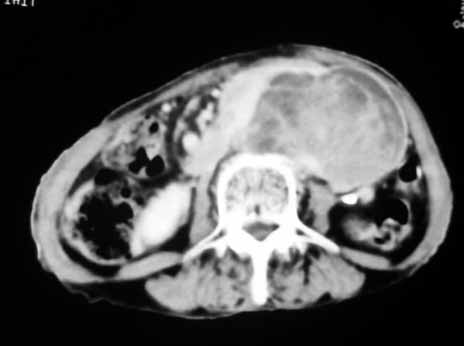

以下是引用天南地北在2007-4-30 17:42:00的发言:[br]增强扫描显示腹主动脉给包绕、推移。肿块不规则强化,[br]修正我在平扫的诊断[br]支持考虑:间叶源性肿瘤可能性大

以下是引用余辉在2007-4-30 18:01:00的发言:[br]病灶前方的条状增强影是什么?若是胰腺,位置似乎有点低,若是十二指肠,似乎又不诫该是那样强化,姑且将其看作胰腺吧,那么考虑来源于胰腺粘液囊腺瘤可能性大,其次考虑来源于肠系膜或者后腹膜的肿瘤如平滑肌肉瘤,异位嗜铬细胞瘤及淋巴瘤等。

以下是引用zyx168在2007-4-30 23:24:00的发言:[br]考虑:间叶源性肿瘤可能性大